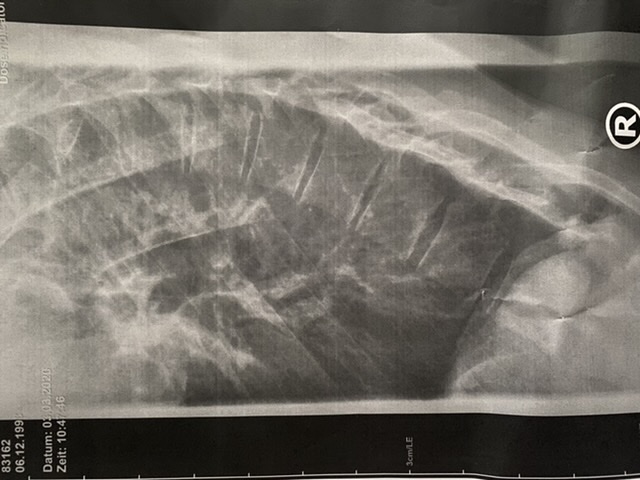

Nun habe ich hier im Forum sehr viel gelesen und bekomme immer mehr Sorgen bei dem was ich alles so lese... echt üble Geschichten dabei. Ich habe mir darauf von meinem Orthopäden die Röntgenbilder zuschicken lassen (leider keine Ganzaufnahme) und wollte fragen ob ihr auf diesem Bild einen Keilwirbel erkennen könnt? Ich bin zurzeit voller Sorge das ich an meinem Rücken nicht mehr viel machen kann wenn ich schon Keilwirbel habe. Mein Termin in Leonberg bei Frau Richthofen ist erst in 1 1/2 Monaten und solange zu warten fällt mir echt schwer.

Ich hoffe ihr könnt das Bild beurteilen

Zunächst mal ist es für eine Behandlung nicht wichtig, ob es ein Scheuermann war, der den Rundrücken verursacht hat. Keilwirbel könnten je nach Lage und Anzahl eine Behandlung erschweren, aber das würde an der Behandlung nichts ändern. Ich sehe aber keine.

Einen Morbus Scheuermann hat sie auf den vorgelegten alten Röntgenbildern nicht erkannt. Bei der von ihr angefertigen Röntgenbildern hatte sie nichts mehr zu Keilwirbeln etc. gesagt. Ich hänge das Röntgenbild als Anhang an.

Hyperkyphose: eingestelltes Röntgenbild, Diagnose 70 Grad

Hyperlordose: laut Diagnose offensichtlich keine vorhanden, ist bei Hyperkyphose ungewöhnlich, deswegen meine Nachfrage